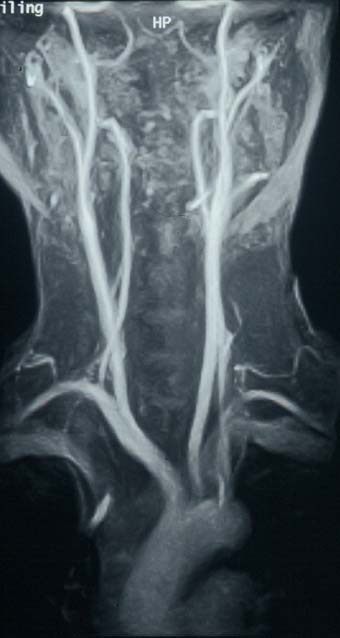

Magnetic resonance angiography

Magnetic resonance angiography (MRI and MRA) is one of the newer techniques whic also provide a road map of the arteries. It is a technically complicated imaging method which relies on powerful magnets to align water molecules in the body tissues. It is a painless and fairly rapid form of assessment especially on the latest machines, but is noisy and some patients feel hemmed in or claustrophobic by the procedure.

It can be used to assess almost any artery in the body but has been found particularly useful in the assessment of carotid artery disease, as shown on the right. It is also good for assessing the renal (kidney) arteries. It does not require puncture of an artery and consequently is only useful in the diagnosis of disease and cannot be used to treat arterial problems.

MRA is becoming an increasingly popular imaging technique for blood vessels. Some recent reports indicate there is a risk of kidney damage in some patients from the use of a gadolinium contrast medium.